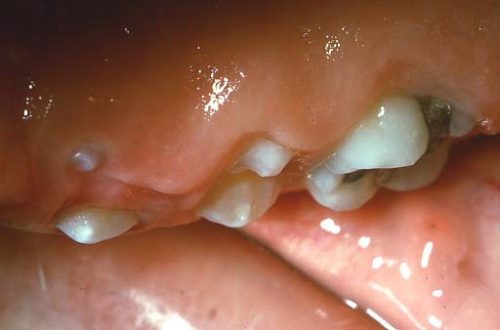

فیبروماتوز ارثی لثه

این بیماری یک وضعیت نادر وراثتی است که معمولا در کودکی ایجاد میشود. اگر چه برخی موارد آن ممکن است تا بزرگسالی مشهود نشوند. در این وضعیت رشد کند عمومی یا گه گاهی محلی لثه مشاهده میشود که بدون حساسیت در حین لمس بوده و لثه سفت و به رنگ صورتی کمرنگ است. نمونه ای از این وضعیت در شکل زیر مشاهده میوشد که نشان میدهد چگونه دندانها توسط رشد بیش از حد لثه پوشانده شده اند.

اغلب برای جلوگیری از نهفته شدن دندانها یا جا به جایی آنها بافت اضافی لثه به روش جراحی برداشته میشود. جراحی مکرر برای برداشتن بافت زیادی لثه ممکن است لازم باشد چون ماهیت این وضعیت عود شونده است.